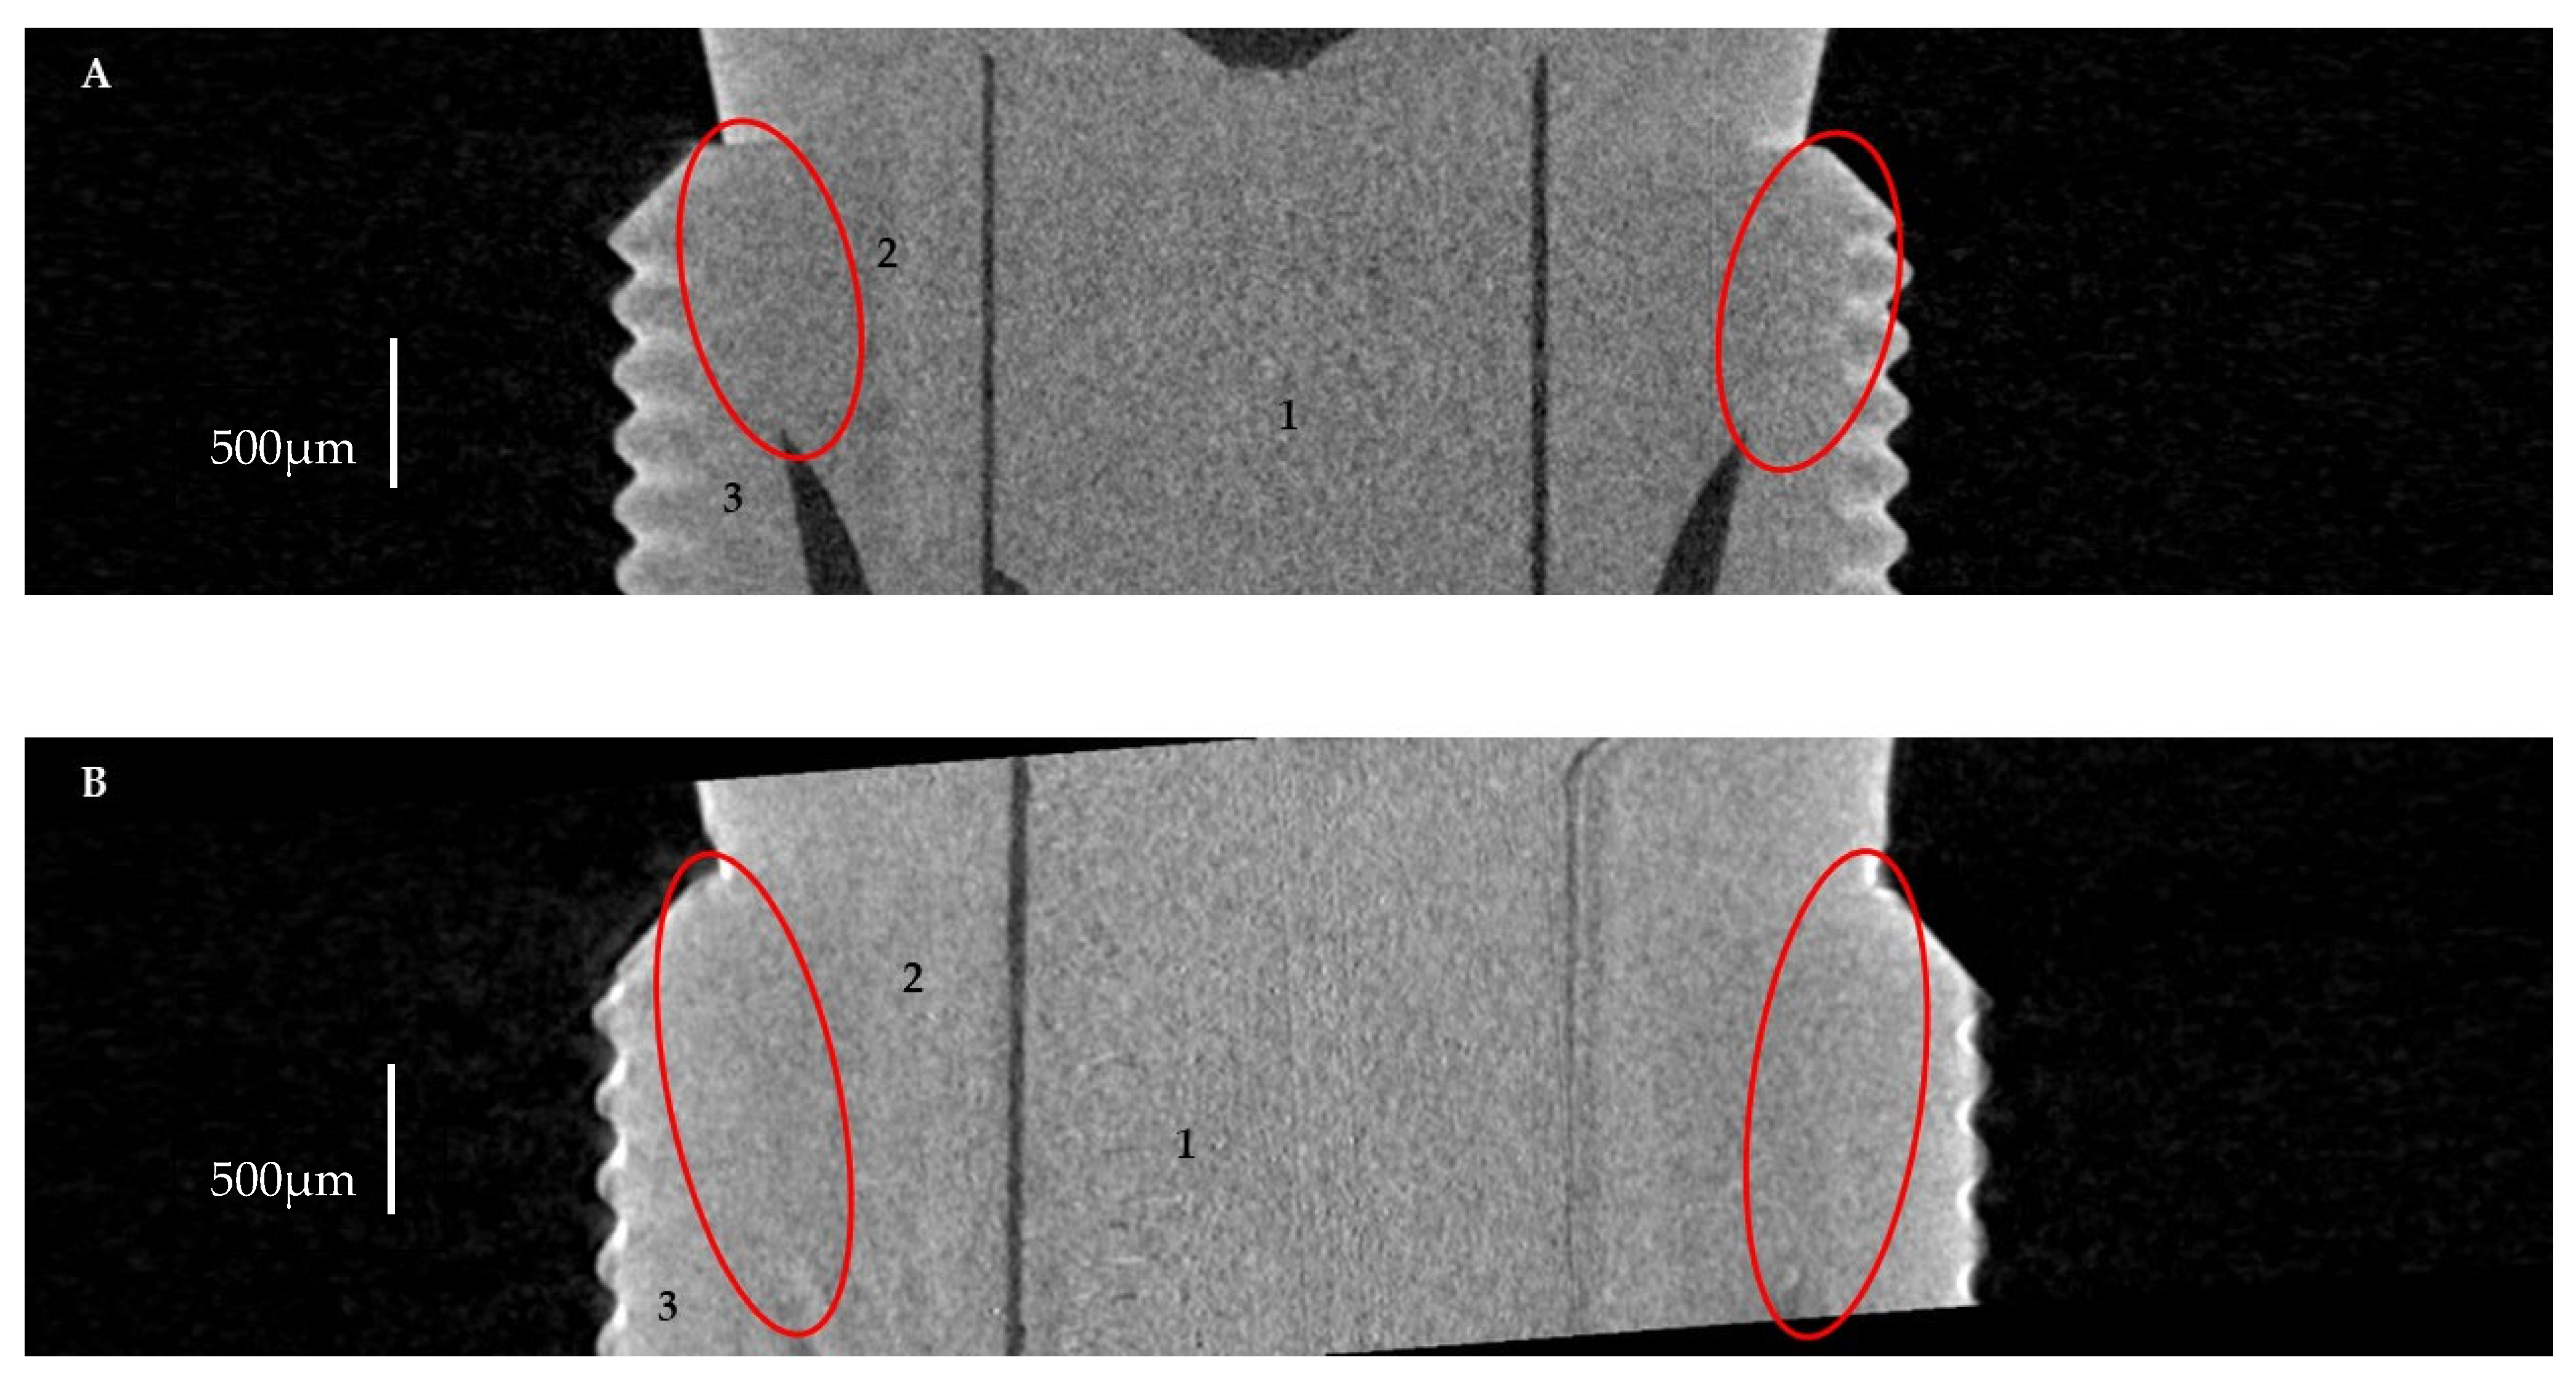

2.2.1. Horizontal Microgap (Linear Measurement)

3.1. Horizontal Microgap (Linear Measurement)